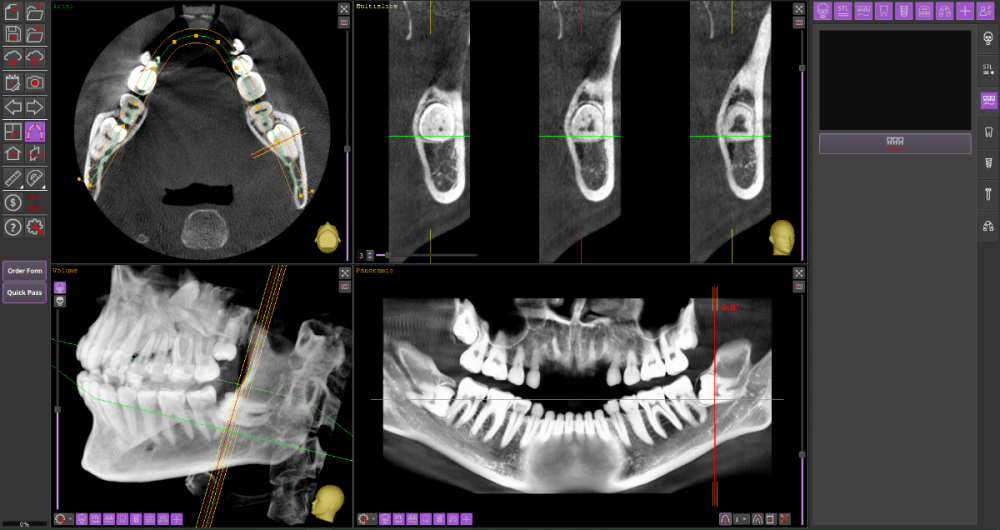

Прошу Вашего совета по поводу удаления восьмых зубов.

Из жалоб есть непродолжительная ноющая боль в правой нижней челюсти, не связанная с внешними раздражителями.

1. Необходимо ли удаление зубов мудрости?

2. Возможно ли удаление амбулаторно, без общего наркоза?

3. Нет ли риска для семёрок при удалении.

DICOM во вложении на Яндекс.Диске https://disk.yandex.ru/d/mBS1B4TYMHIf1A

Виновником боли в н.ч. справа может быть, например зуб 46, не только 48.

1. Удаление 8-х зубов скорее всего необходимо

2. Удаление амбулаторно вполне возможно. Общая анестезия (наркоз) совершенно необязательна, местной анестезии достаточно.

3. Несчастные случаи бывают, но крайне редко.